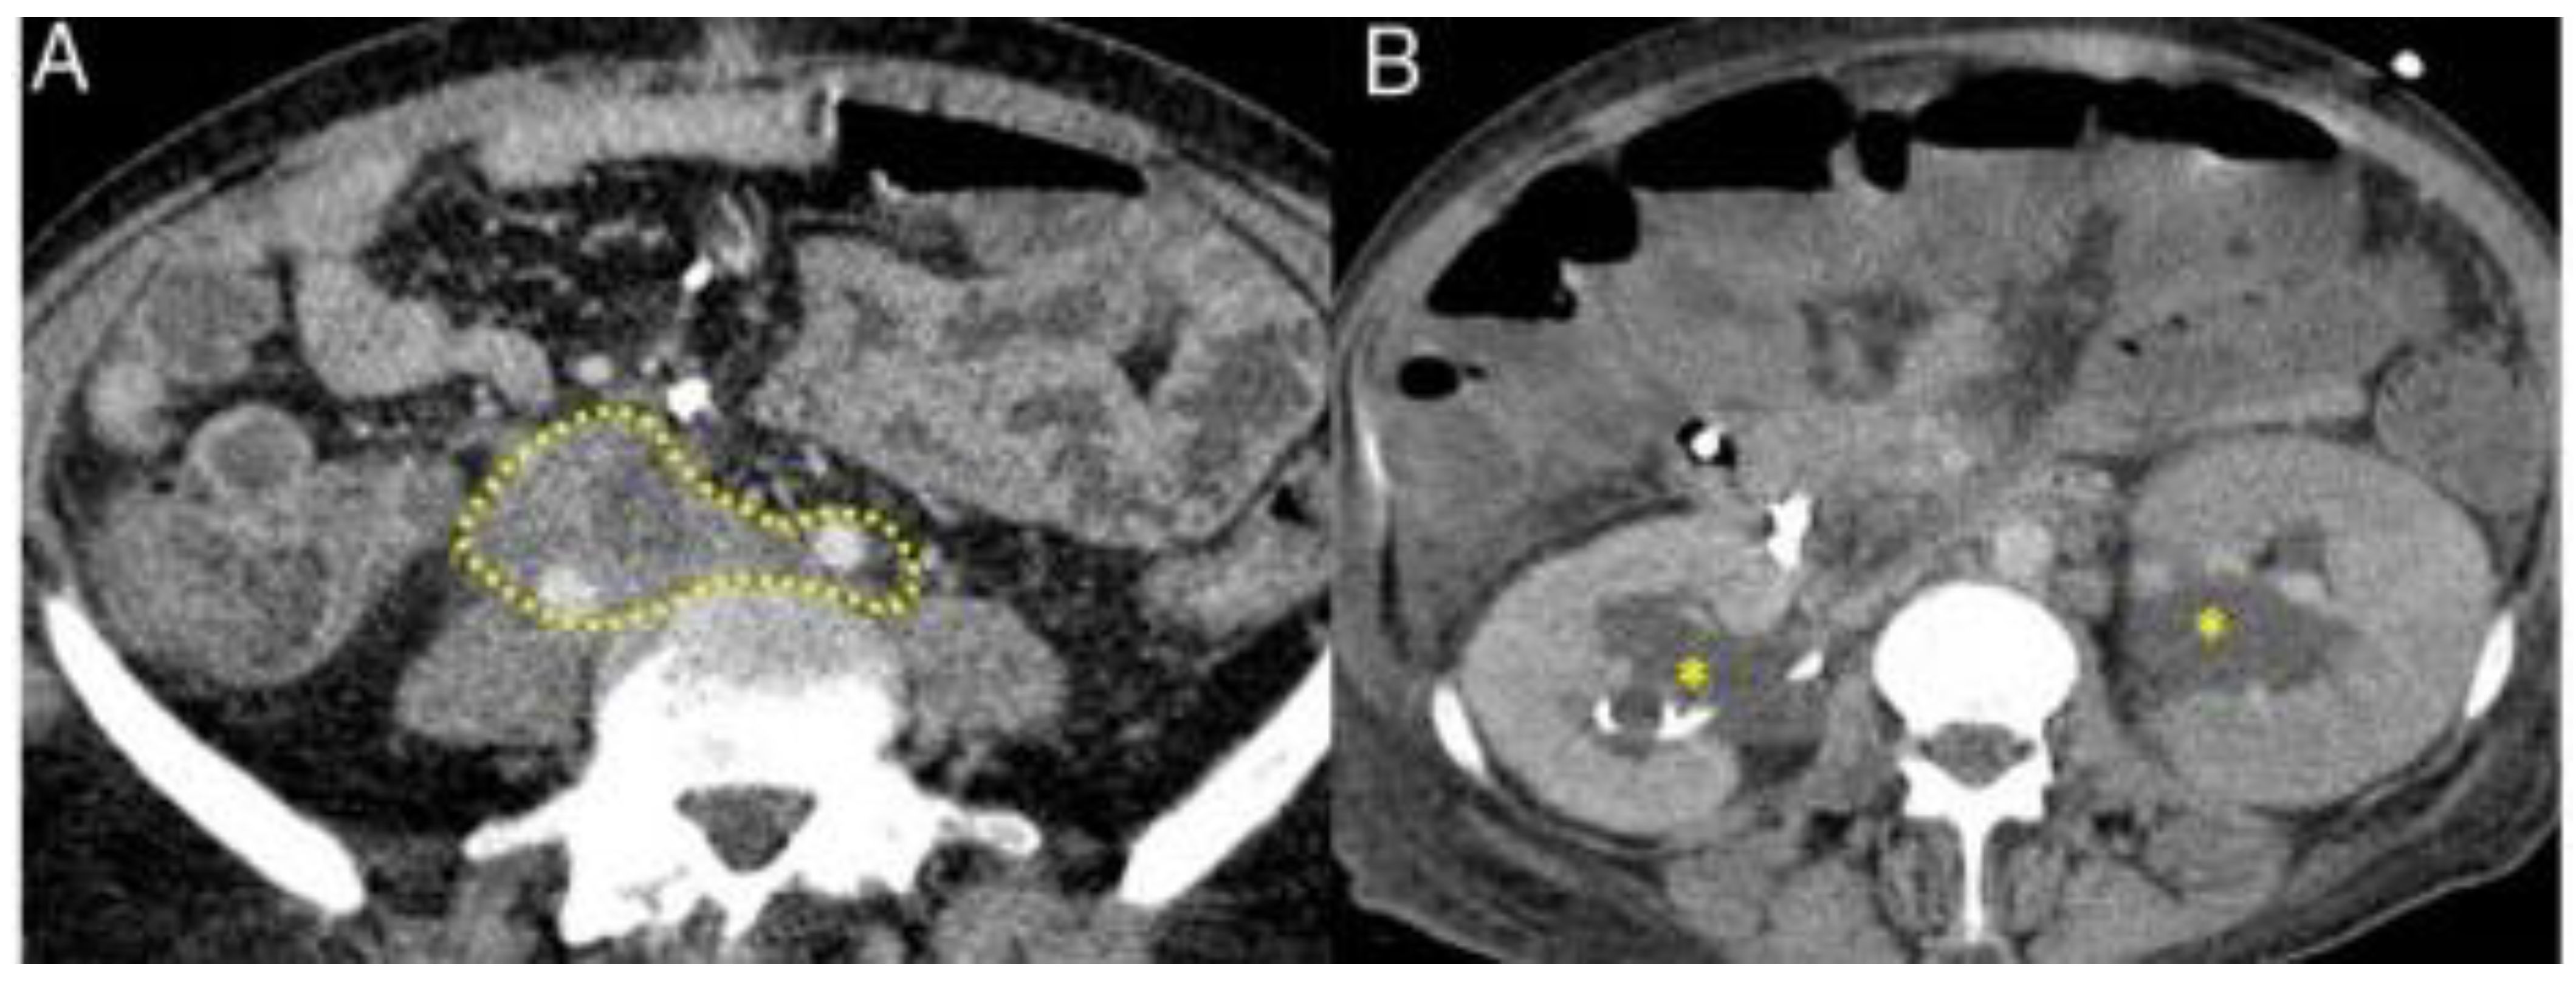

3.2.5. Retroperitoneum

3.3.5. Retroperitoneum